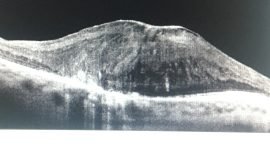

Malattie della Macula o Maculopatia – Dr. Elia Lo Schiavo Oc